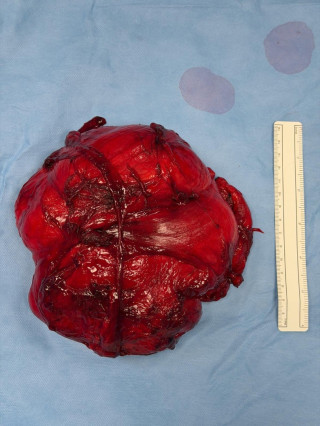

Case presentation

A 72-year-old male patient presented with acute onset of thoracic and abdominal pain, additionally complaining of light-headedness and cold sweats. The medical history was unremarkable regarding previous trauma or infections, but the patients was recently diagnosed with a kidney mass. The patient was hypotensive, tachycardic, with cold peripheral extremities and tenderness in the epigastrium. Laboratory investigations showed mild anaemia and leucocytosis, impaired renal function, and high lactate. Ultrasonography suggested free fluid in the Morison’s pouch, a mass of the left kidney and inhomogeneous splenic tissue, confirmed by CT angiography, which revealed a hematoma of the spleen with signs of ongoing bleeding and free fluid in the abdominal cavity.

After initial stabilization with blood transfusions and phenylephrine, an endovascular approach was planned. However, the patient developed hypovolemic shock prior to the procedure, indicating urgent explorative laparotomy. After the splenic hilum was initially clamped, splenectomy was performed, resulting in hemodynamic stabilization. Subsequent exploration of the abdomen revealed peritoneal nodules and a tumour of the left kidney. Peritoneal biopsies were taken and showed a papillary renal cell carcinoma. The patient was referred for further diagnostic and treatment to the oncology department to receive chemotherapy.

The postoperative recovery was uneventful except for one additional blood transfusion and the patient was discharged on postoperative day six.